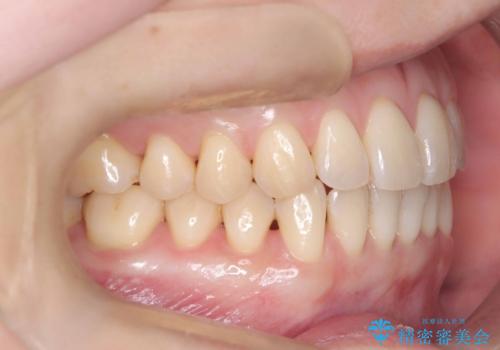

昔から食いしばりがあるのを患者様が自覚されており、そのせいか口が開けにくいことも悩まれていました。

インビザラインの性質上、食いしばりや歯ぎしりがある方は咬み合わせが甘くなることがあります。そのような時は保定装置にベックタイプのリテーナーを組み合わせることで改善できます。